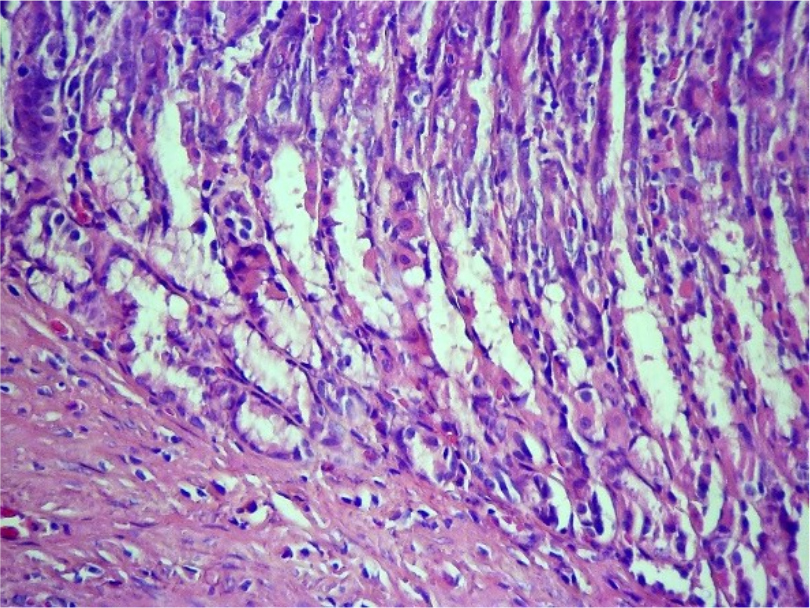

При проведении патоморфологического исследования у животных из второй группы на 3-й день было выявлено, что поверхностный железистый эпителий слизистой оболочки в состоянии атрофии, тотально слущивается (Рис.5). Эпителий, выстилающий железы представлен в основном слизистыми экзокриноцитами, что придает железам пенистый вид, просветы желез расширены. Очагово отмечается атрофия и слущивание эпителия, также присутствуют фокусы гомогенизации желез – отек. Васкуляризация стенки желудка активная. Сосуды гиперемированы, в слизистой оболочке в собственно-слизистом слое отмечается стаз крови в капиллярах.

Рис. 5. Атрофия и слущивание поверхностного эпителия. Ув. ×200